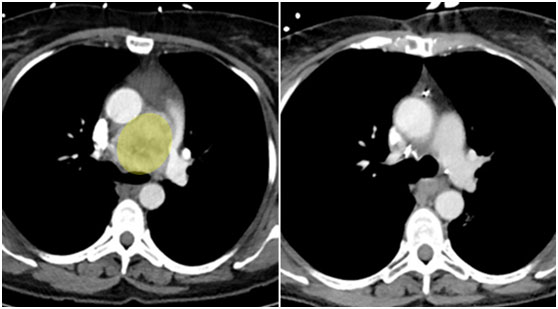

在放射治療前,腫瘤有網球大小(左圖)。即使治療使腫瘤縮小(右),醫(yī)生仍然需要完成手術。

Brigitte Coles的心臟和肺之間長了一個網球大小的腫塊,它包裹著主動脈。這個腫瘤的位置太兇險了,對醫(yī)生來說無疑是個罕見的重大挑戰(zhàn)??死蛱m診所胸外科專家Daniel Raymond博士事后坦言:“手術之前,誰都不能確保無虞,我們心里也沒什么底。”